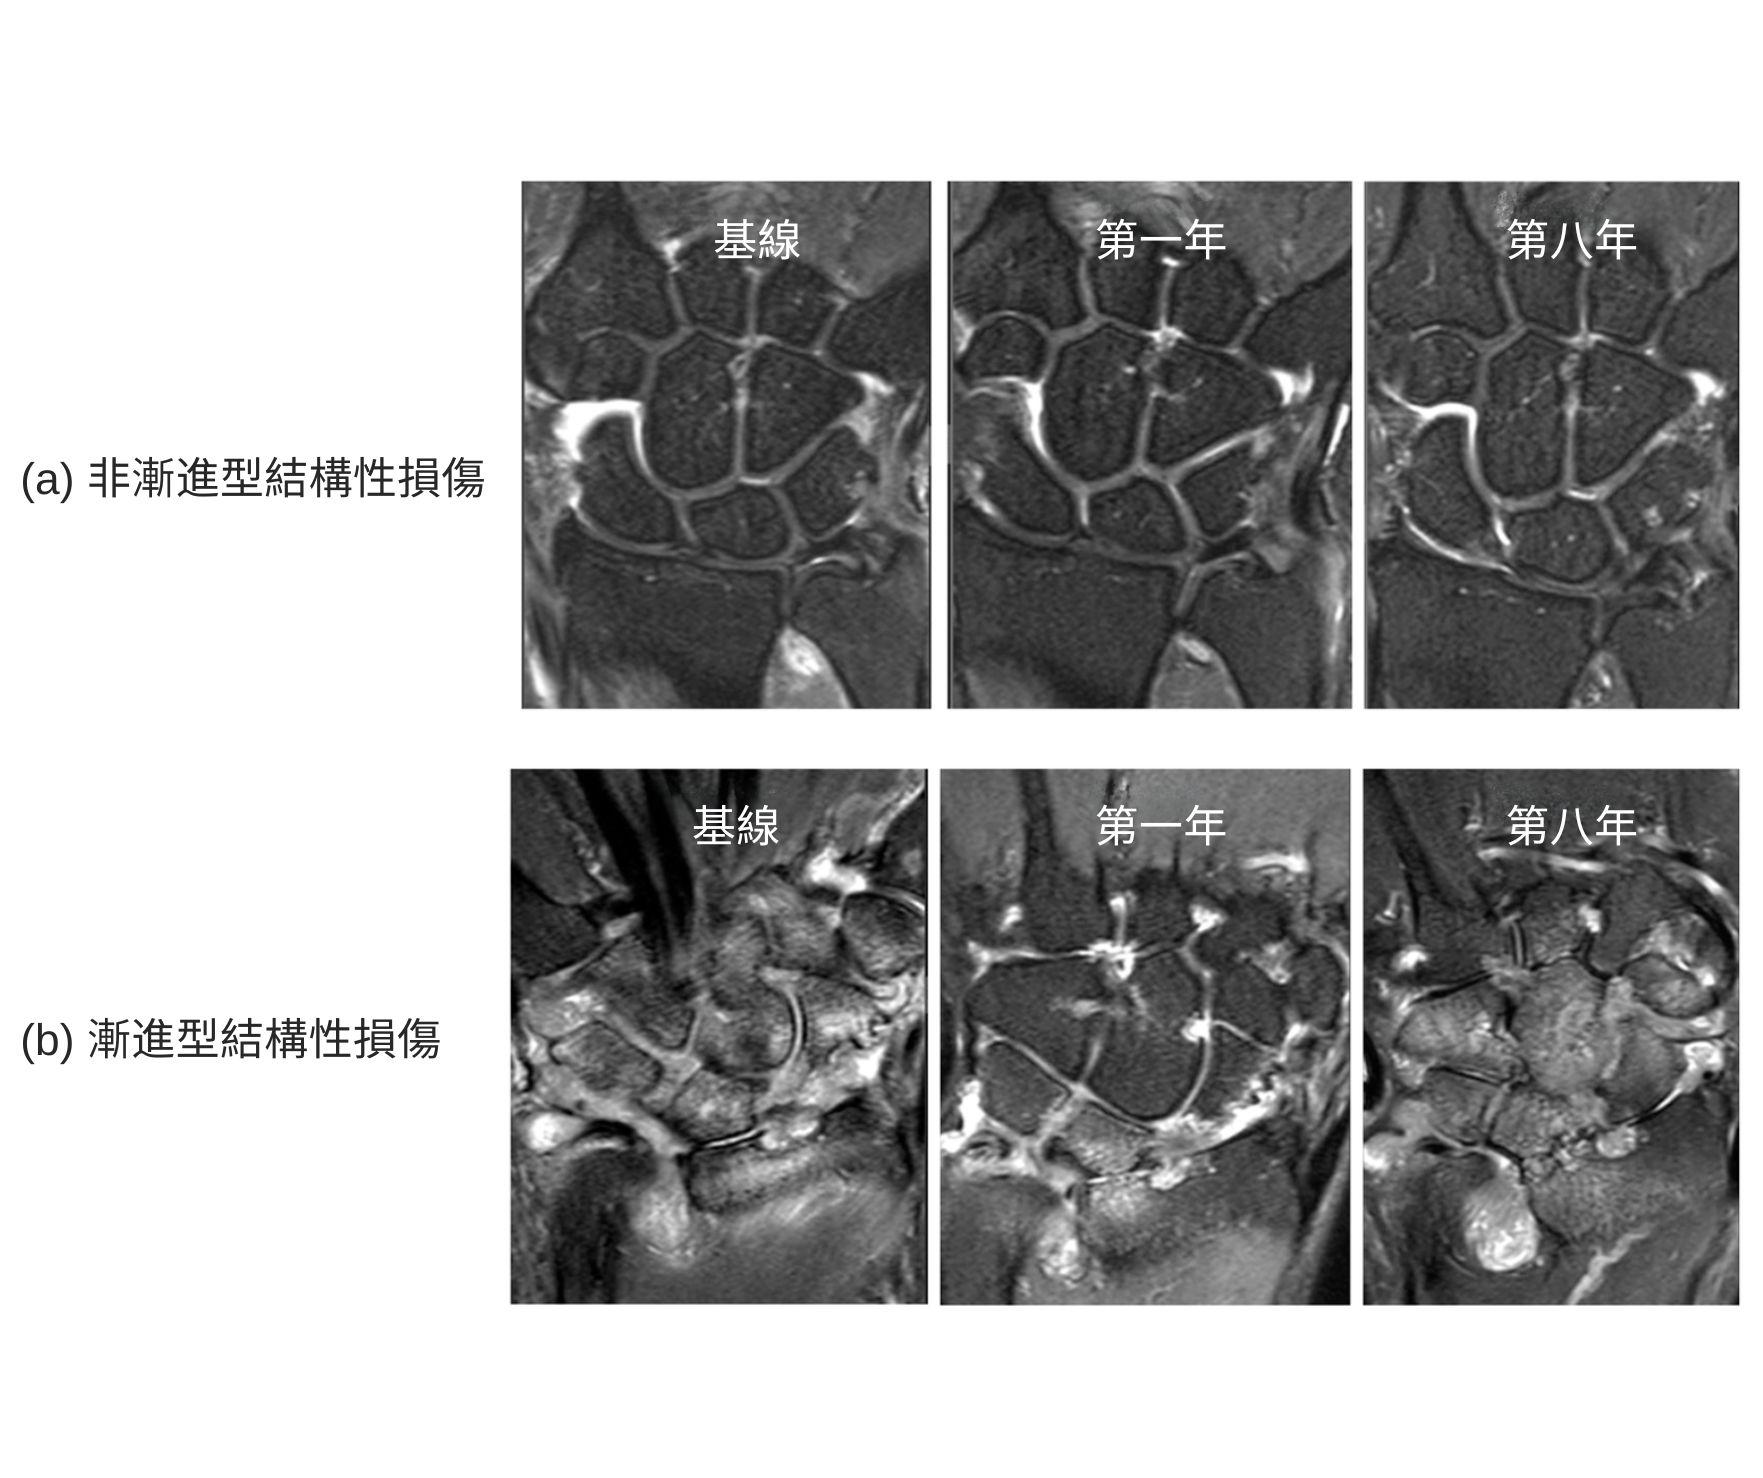

研究招募了81名初期類風濕關節炎患,其病徵出現時間均少於24個月,並於治療前、第一年及第八年接受磁力共振掃描,以全面評估炎症及結構性關節的損傷。結果顯示,類風濕關節炎的病情發展可分為兩大類型,與發炎的嚴重程度隨時間的變化有關。約三分之二的患者呈現非漸進型結構損傷(「非漸進型患者」),初次求診時的磁力共振影像顯示結構性損傷屬輕微,而這些患者在8年的跟進期內未再出現關節變形。

其餘三分之一的患者則出現漸進型結構損傷(「漸進型患者」),初次求診時的磁力共振評估顯示中至重度的關節損傷。即使這些病人已接受調理免疫系統的藥物治療,病情仍持續惡化。及至第八年,漸進型患者的功能受損比率更是非漸進型患者的兩倍。在初次求診時,漸進型患者的關節早已嚴重變形,反映此類患者確診時已為時過晚。